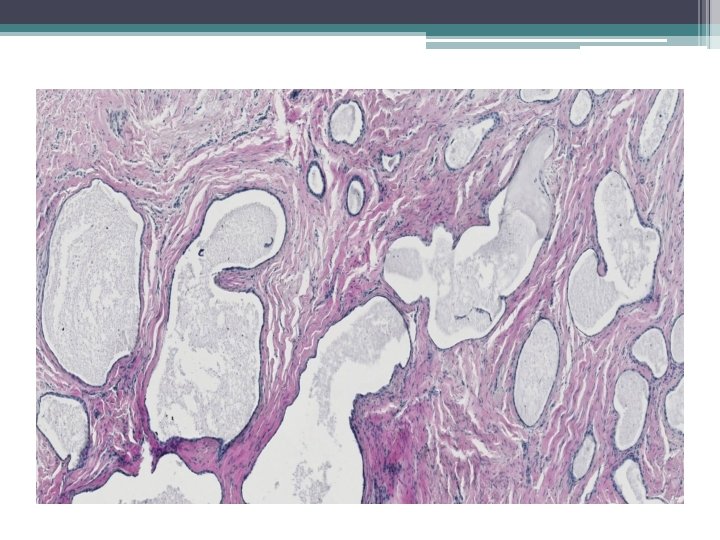

Mikro:

Ektopická prostatická tkáň • • vzácně lokalizace: cervix, vagína věk 21 -65 let mikroskopicky : tubuly a aciny některé papilární, některé kribriformní, s dlaždicovou metaplázií

• Mikroskopicky: • dobře ohraničená hnízda s vrstevnatým dlaždicovým epitelem a tubuly vystlané jednou až dvěma řady kubických buněk, nebo dlaždicovými buňkami. V centru hnízd může byť přítomná nekróza s kalcifikací, nebo keratinové perly.